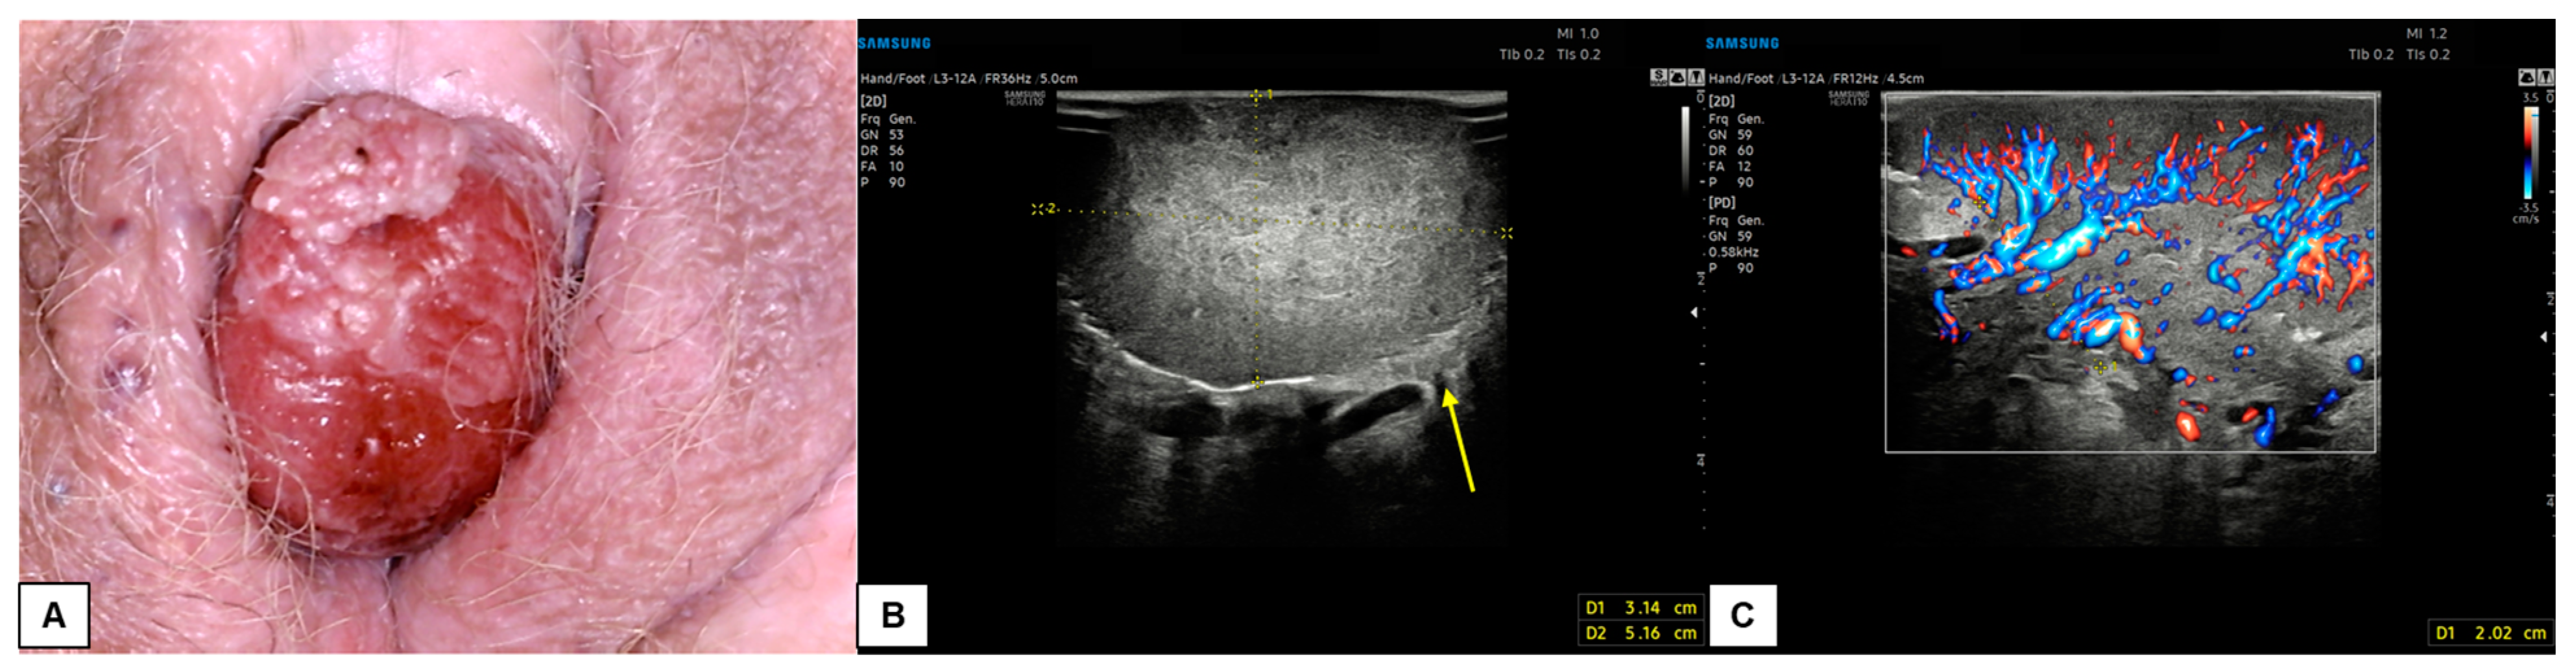

7.3. Malignant Vulvar Lesions